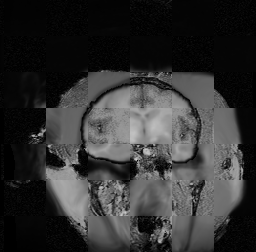

For each of the 10 subjects, we show checkerboard slices in each direction (1) before registration, first row; (2) after rigid->scaleversor->affine registration, second row; and (3) after BSpline registration, third row.

Note the unsuccessful BSpline registration result for Issac.

Issac

Issac is a good example of BSpline registration failure.

Ron noted, the reason might be that Issac had his mouth open, unlike most of the subjects registered successfully.